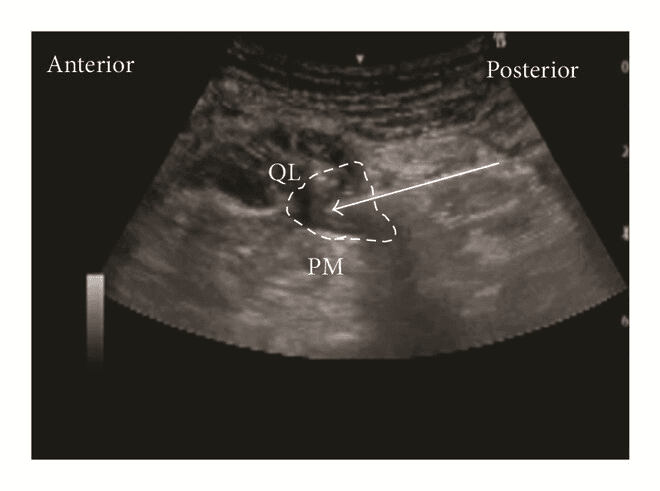

Задня QL-блокада (тип 2 QLВ, QLB2)

Для QLВ2 конвексний/лінійний датчик розташовують в поперечній площині по середньоаксилярній лінії та зміщують назад, як і при QLB1, доки не стане видимим задній край квадратного м'яза попереку. Голку вводять in-plane з латеральної сторони датчика до моменту, коли її кінчик опиниться біля заднього краю m. quadratus lumborum. Місцевий анестетик вводять в середній шар тораколюмбальної фасції поблизу поперекового міжфасціального трикутника (LIFT). Правильне розміщення кінчика голки має призвести до поширення місцевого анестетика вздовж середнього шару fascia thoracolumbalis до паравертебрального простору.